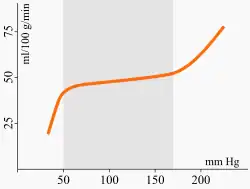

Eines der „Sicherheitssysteme“ zum Schutz vor zu geringer, aber auch zu hoher Perfusion ist die Autoregulation der Hirndurchblutung. Die Widerstandsgefäße halten den effektiven Blutdruck im Gehirn (den sogenannten Perfusionsdruck, der sich aus der Differenz zwischen dem systemischen Blutdruck und dem intrakraniellen Druck ergibt) durch verschiedene komplex zusammenspielende Steuerungsmechanismen nahezu konstant, während der systemische Blutdruck zwischen 50 und 170 mmHg schwanken kann. Zu diesen gehören der Bayliss-Effekt, die Regulation durch die sympathische und parasympathische Innervation der größeren Gefäße und direkt auf die Myozyten der Glatten Muskulatur wirkende endokrine und chemische Faktoren (pH-Wert, Adenosin, Kalium und weitere). Die Grenzen dieser Anpassung verschieben sich bei dauerhaftem Bluthochdruck nach oben; durch langbestehenden, schlecht eingestellten Diabetes mellitus kann das Autoregulationsvermögen insgesamt gestört sein.[9]